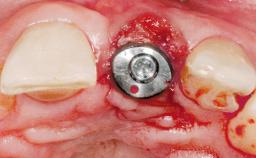

Immediate Placement of an Implant in a Maxillary Right Central Incisor Site

A 30-year-old female patient was referred to the office for the treatment of tooth 11. Her chief concern at the initial visit was to inquire, “Why is my tooth pink?” Upon clinical examination, it was determined that tooth 11 had a previous history of trauma and that the clinical crown had become noticeably pink in color as a result of internal resorption. This diagnosis was confirmed radiographically, indicating a large radiolucency involving the central and distal portions of the clinical crown. It was determined that restoration of this tooth was not possible, and that extraction was indicated. The presence of a mid-line diastema, which the patient wanted to reproduce, directed the treatment plan for tooth replacement utilizing a dental implant.

Type of Implants One-Piece|Reduced-Diameter

Attachment One-Piece|Reduced-Diameter

Abutment Type Standard

Placement Protocol Immediate implant placement

Tooth Site Maxillary incisor or canine